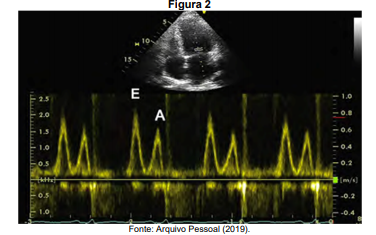

Paciente de 62 anos, portador de miocardiopatia dilatada de etilogia chagásica. Sua fração de ejeção estimada pelo método Simpsom é de 32%.

Dados complementares:

E/E’: 17

Velocidade max tricúspide: 3,2 m/s

Volume atrial: 42 ml/m2.

De acordo com as últimas diretrizes de avaliação diastólica, considerando a análise do fluxo mitral da figura 2 e os dados fornecidos, é correto afirmar que